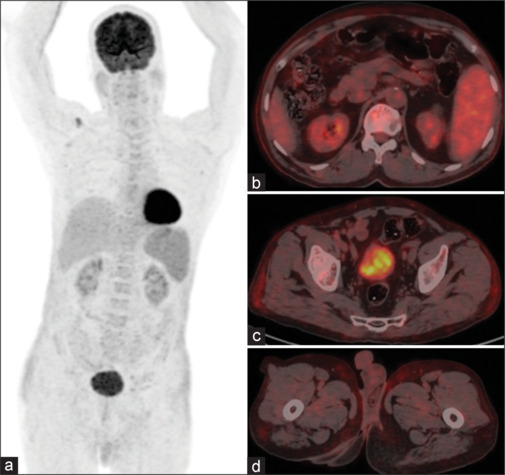

White adipose tissue (WAT) generally has negligible glucose utilization and thus, shows no or insignificant Fluorine-18 fluoro D-glucose (FDG) uptake. However, corticosteroids can cause altered biodistribution of FDG with increased uptake in WAT. We hereby describe a case of immune complex-mediated glomerulonephritis showing diffusely increased FDG uptake in WAT secondary to high-dose corticosteroid therapy.